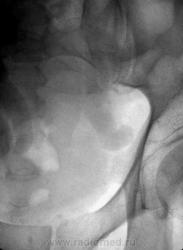

Может быть два варианта - в уретероцеле или в дивертикуле мочевого пузыря. А слева блок где-то в области устья... Двусторонний гидроуретеронефроз II.

Справа 2 конкремента - в средней трети и внизу - в дивертикуле мочевого пузыря или в уретероцеле. Слева неясной природы предпузырный блок, + двусторонний гидроуретеронефроз второй стадии.

Больше всего в этом случае меня как бы смущает "завернутость" дистальных отделов мочеточников наружу. Полагаю - это следствие удлинения.....

Камня в левом мочеточнике ро-позитивного не видно, перегибы мочеточников могли бы дать такую клинику. Пусть узи-сты посмотрят еще нет ли нефроптоза. И я с вами согласна странно что мочеточники так сротированы но не наружу а вовнутрь .

Что оттесняет правый мочеточник, как раз понятно - в дивертикуле плавает камень. Непонятно, где мочевой пузырь? Такое слабое его контрастирование?

Мочевой пузырь контрастирован, правда очень слабо, но тем не менее, присмотритесь. А почему слабо - так ведь ТАКОЕ нарушение оттока.

Довольно часто встречается мегауретер. Наиболее важным патогенетическим фактором в развитии этой аномалии следует считать врожденную нервно-мышечную слабость стенки мочеточника. Она всегда сочетается со стриктурой интрамурального отдела мочеточника.

В развитии болезни выделяют 3 стадии. Начальной его стадией является ахалазия мочеточника. Это стадия компенсации, так как нарушена уродинамика только нижнего цистоида. Во второй стадии (мегалоуретер) мочеточник расширен на всем протяжении, т. е. исчерпаны компенсаторные возможности мышечной оболочки. В третьей стадии развивается гидроуретеронефроз.

Данный порок развития в большинстве случаев бывает двусторонним. Застой мочи и частый пузырно-мочеточниковый рефлюкс предрасполагают к инфекции и нарастающей почечной недостаточности.